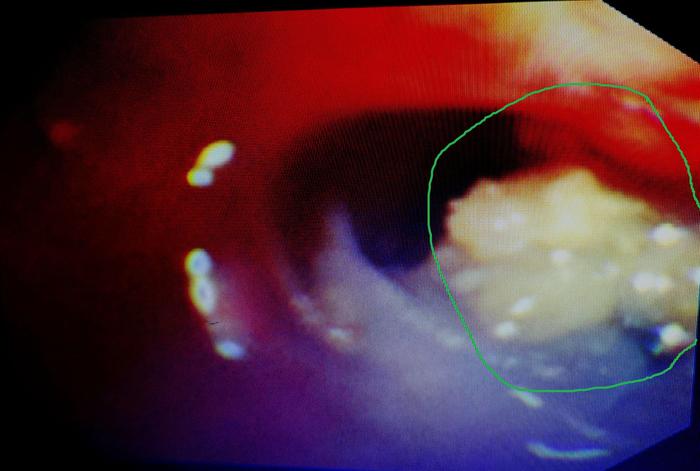

患者女,55岁,因“咯血半个月”入院。

入院后查血常规、凝血功能、D-二聚体、心电图均正常。胸部CT如下:

图1

胸部CT仅见左肺上叶少许炎性改变,这种很常见的影像改变,非常容易让人大意以为就是普通的细菌感染而造成漏诊或误诊。

其实够用心或者有足够经验就会意识到,这点病灶不至于引起这样的咯血。为了明确咯血原因,我们给她做了支气管镜检查,虽然病灶在支气管的远端,支气管镜下未发现异常,但我们常规给予支气管肺泡灌洗液(BALF)送检。

支气管肺泡灌洗液培养结果回报有“出人意料”的重要大发现——见到黄曲霉。

于是我们换4.0mm直径的细支气管镜进入该支气管亚段再次检查,发现左上叶上舌段亚段内白色坏死物,为了进一步确诊,我们给予钳检。

图2

钳检病理回报见真菌孢子及菌丝样物,故该患者实际上不是细菌感染,而是曲霉菌感染所致,治疗上予注射用伏立康唑(0.2g,每日2次)治疗。50天后复查支气管镜,原病灶处明显好转,气管镜下予伏立康唑局部注射治疗。

图3

这个病例告诉我们对于不明原因的咯血不要忽略了做支气管镜检查,同时提醒我们就算支气管镜下未发现病灶,也很有必要在相应的可疑部位做灌洗留取标本检查协诊。

此外,笔者还想提醒大家的是,支气管肺泡灌洗液半乳甘露聚糖(GM)测定对肺曲霉病的诊断具有较高的敏感度和特异度,千万别满足于只做常规的涂片和培养。